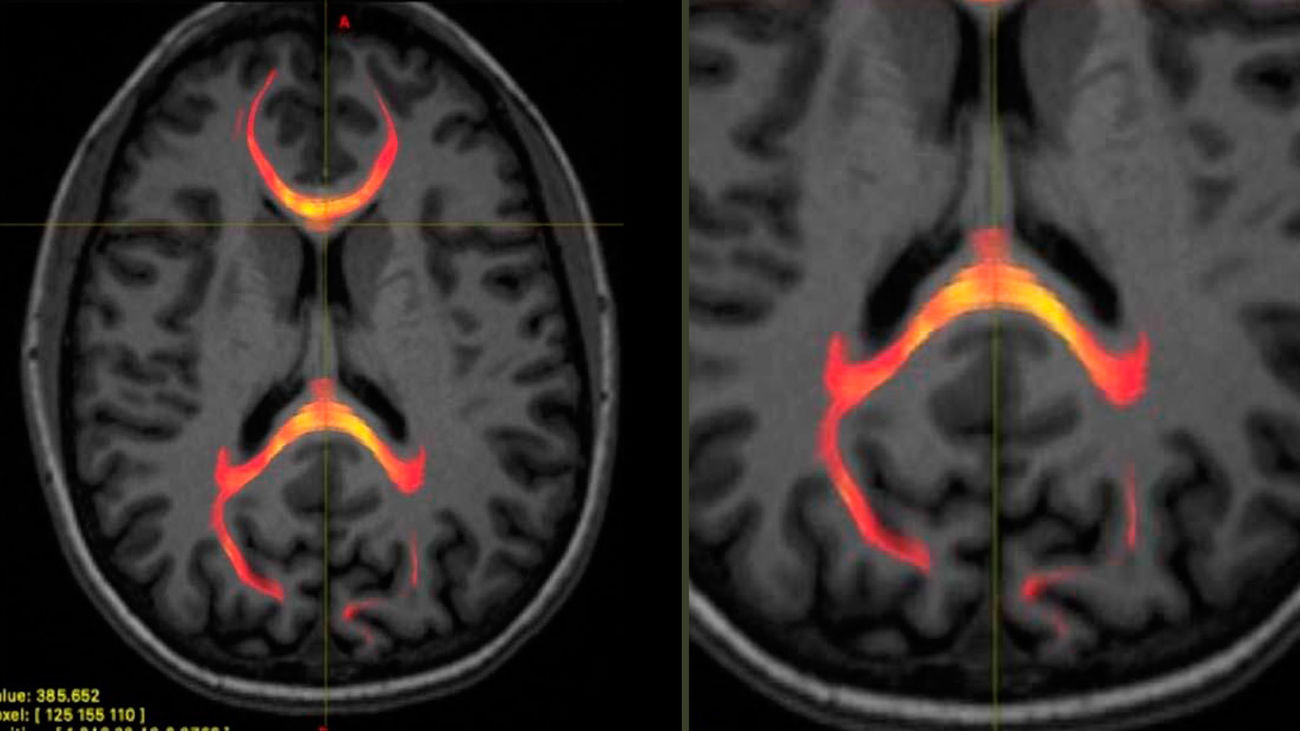

Imagen de RMN de un paciente con lesión cerebral

Imagen de RMN de un paciente con lesión cerebral |RSNA